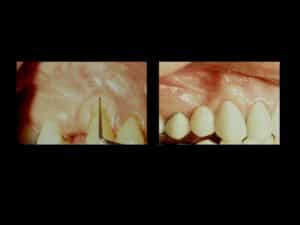

Before Gum Graft Surgery

After Gum Graft Surgery

Soft Tissue Grafts can be used to cover exposed roots and handle excessive gingival recession that is the reason for the lack of gum tissue. The procedure assists in developing additional gum tissue. During gum graft surgery, Dr. Fialkoff will cover the exposed root for one tooth or several teeth. The goal is to even your gum line and reduce the sensitivity in your mouth.

Please note that covering the roots is unpredictable and no guarantee can be given as to the final coverage or lack of. These pictures are only examples and not guaranteed results.